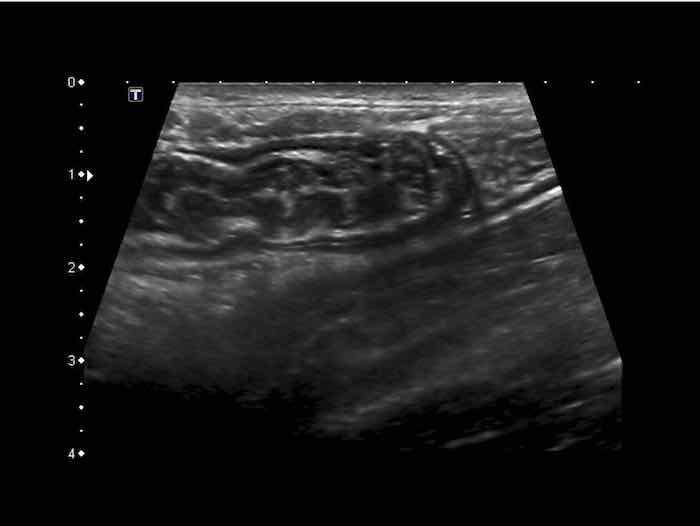

Đây là hình ảnh siêu âm của một trẻ 2 tuổi bị lồng ruột hồi manh tràng từng đợt, được khám trong khoảng thời gian giữa các cơn.

Hồi tràng với nhiều mảng Peyer sa vào manh tràng.

Hình ảnh siêu âm kinh điển của lồng ruột hồi-manh tràng ở hai trẻ khác nhau.

Trong cả hai trường hợp, đoạn hồi tràng bị lồng được định vị không đối xứng bên trong ống lồng ngoài, do mạc treo ruột tăng âm có chứa mỡ, bám vào hồi tràng và đi theo hồi tràng khi bị kéo vào trong.

Trong mạc treo, siêu âm cho thấy một hạch bạch huyết mạc treo (hbh) phóng đại ở cả hai.

Các hạch này phì đại như một phần của tình trạng tăng sản hạch bạch huyết toàn thân và khônghu trú trong lòng hồi tràng.

Do đó đây không phải là điểm dẫn đầu nguyên phát. Ở bệnh nhân bên phải, ruột thừa (mũi tên) cũng bị kéo vào trong.

Lưu ý cấu trúc đa lớp của thành bụng phía trước của phức hợp lồng ruột, đại diện cho ba lớp thành ruột bị gấp lại.